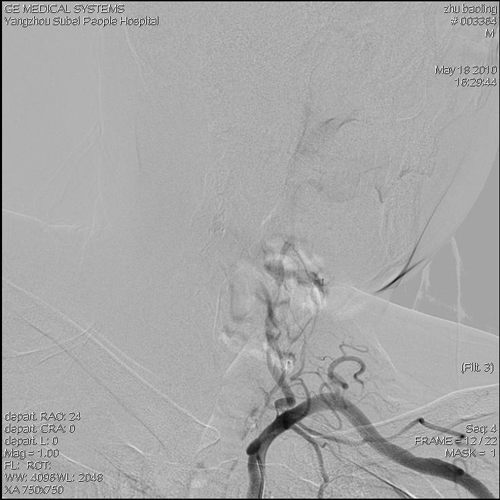

主动脉弓以上血管造影(2010-5-11,本院):动脉粥样硬化改变,左侧颈内动脉近端、左侧椎动脉多发狭窄,椎动脉迂曲。